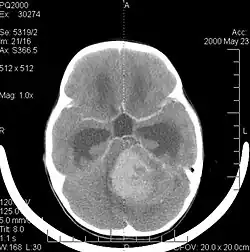

Bildgebung

In der Computertomographie (CT) und Magnetresonanztomographie (MRT) stellen sich Medulloblastome als solide Raumforderungen mit ungleichmäßiger Kontrastmittelaufnahme dar. Sie wachsen meist vom Boden des 4. Ventrikels in den Kleinhirnwurm. Im nativen CT (also ohne Kontrastmittel) ist der Tumor gering hypodens (dunkel), nach Kontrastmittelgabe hyperdens (hell). Im MRT kann man den Tumor aufgrund seiner inhomogenen, symmetrisch in der Mittellinie gelegenen Lage in kraniokaudaler Ausdehnung mit hypointensem (dunklen) Signal in T1 und hyperintensem (hellem) Signal in T2 (weil vermehrt wasserreich) gut erkennen. Oft kommt es zu einer Obstruktion der Ventrikel; als Folge dessen kommt es zum Hydrocephalus. Bei sehr jungen Patienten kann sich dies durch verbreiterte Kalottennähte (Wolkenschädel) zeigen, welche als Konsequenz des steigenden Hirndrucks auseinanderweichen.